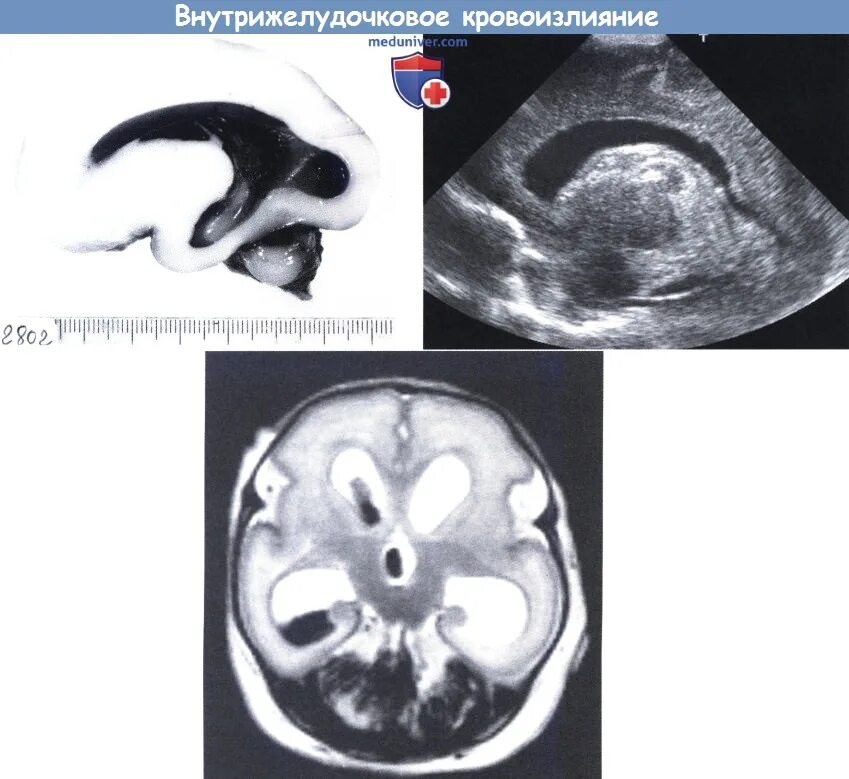

Внутрижелудочковое кровоизлияние